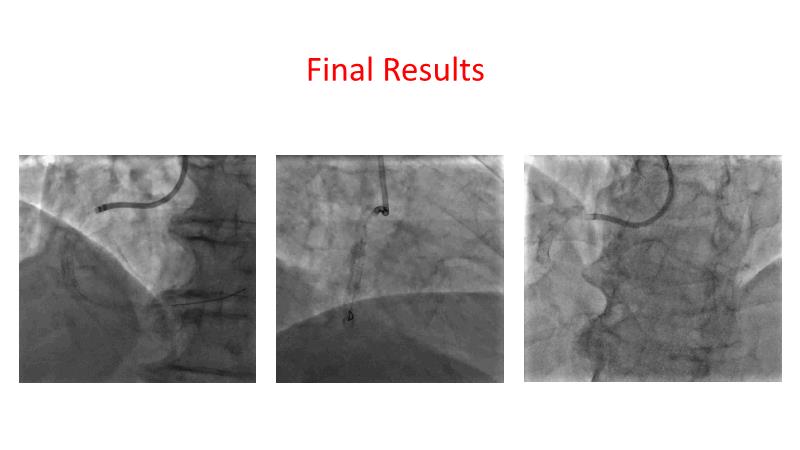

This session is recommended for you if you are seeking insights into the advantages of using IVUS imaging over visual assessment for better outcomes in left main bifurcation procedures. Discuss with experts the benefits of using RotaCUT in lesion preparation for left main bifurcation and explore the impact of high radial strength stents on the procedure's success.

• To know how a high radial strength stent can make a difference in left main bifurcation